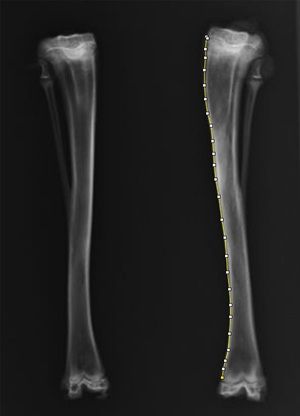

그 결과 성장판에서 10mm 떨어진 부위에 구멍을 내고 뼈 왁스(bone wax)를 채운 경우, 뼈가 정상보다 더 길게 자라는 과성장과 함께 다리가 바깥쪽으로 휘는 외반 변형이 발생했다.

(사진 : 토끼의 좌측 정강이뼈에 작은 구멍을 만들고 방사선학적 평가를 통해 양측 뼈의 길이와 모양을 비교)

반면 구멍을 비워두거나 다른 재료를 사용했을 때는 뚜렷한 길이 변화가 나타나지 않았으며 외반 변형만 관찰됐다.